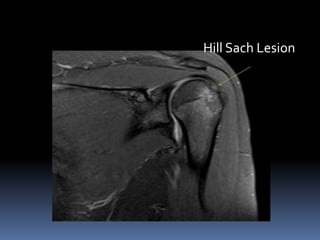

Hill Sach Lesion